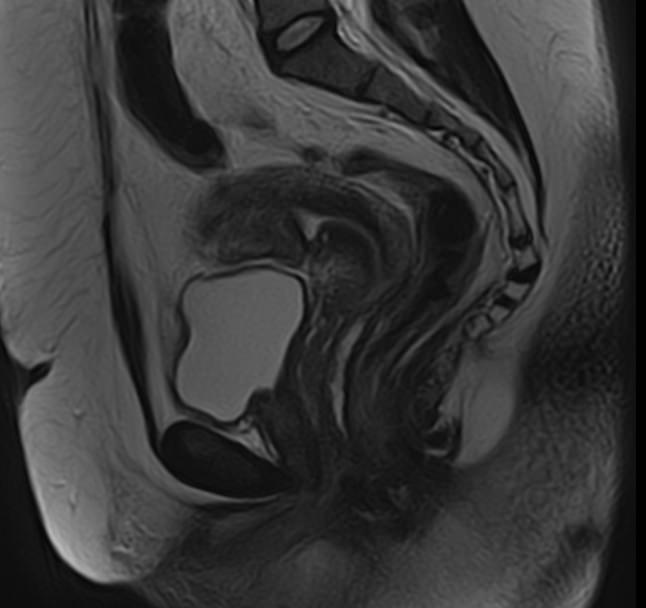

В нашей клинике магнитно-резонансная томография матки проводится при помощи новейшего томографа экспертного уровня TOSHIBA VANTAGE TITAN 1,5 Тесла. Высокая индукция магнитного поля томографа обеспечивает превосходную четкость и детализацию изображений органов женской репродуктивной системы. Отсутствие вредного рентгеновского излучения делает процедуру безопасной и дает возможность проведения исследования неоднократно по мере необходимости.

• Размеры и особенности расположения органа и его придатков.

• Аномалии развития матки (двурогая матка, гипоплазия) и маточных труб.